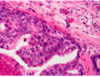

What type of breast cancer is depicted? [1]

classic invasive lobular carcinoma